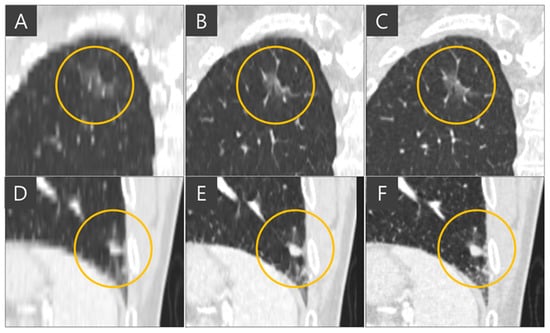

The importance of administration of multiple slices into the network for slice generation is demonstrated in Figure 6. When single slices of coronal CT images are fed into the network, it focuses solely on coronal views and cannot accurately reconstruct images in the sagittal plane, resulting in inaccurate nodule representations when viewed axially. In the ground truth thin-slice CT image and the generated thin-slice CT image produced by the network using sixteen slices simultaneously, a lung vessel passing through a GGN is faithfully reconstructed, preserving both volume and texture. However, the network trained with single-slice inputs failed to accurately reproduce the GGN, resulting in an appearance resembling a subsolid nodule. This highlights the necessity of training the network with multiple slices to capture the full details of three-dimensional CT images.

Figure 6. Axial view of (A) thick-slice, (B) generated thin-slice produced by the model trained on a single slice, (C) generated thin-slice produced by the model train on multiple slices, and (D) thin-slice CT images, subsolid nodules are circled.